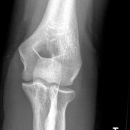

Fat Pad Sign